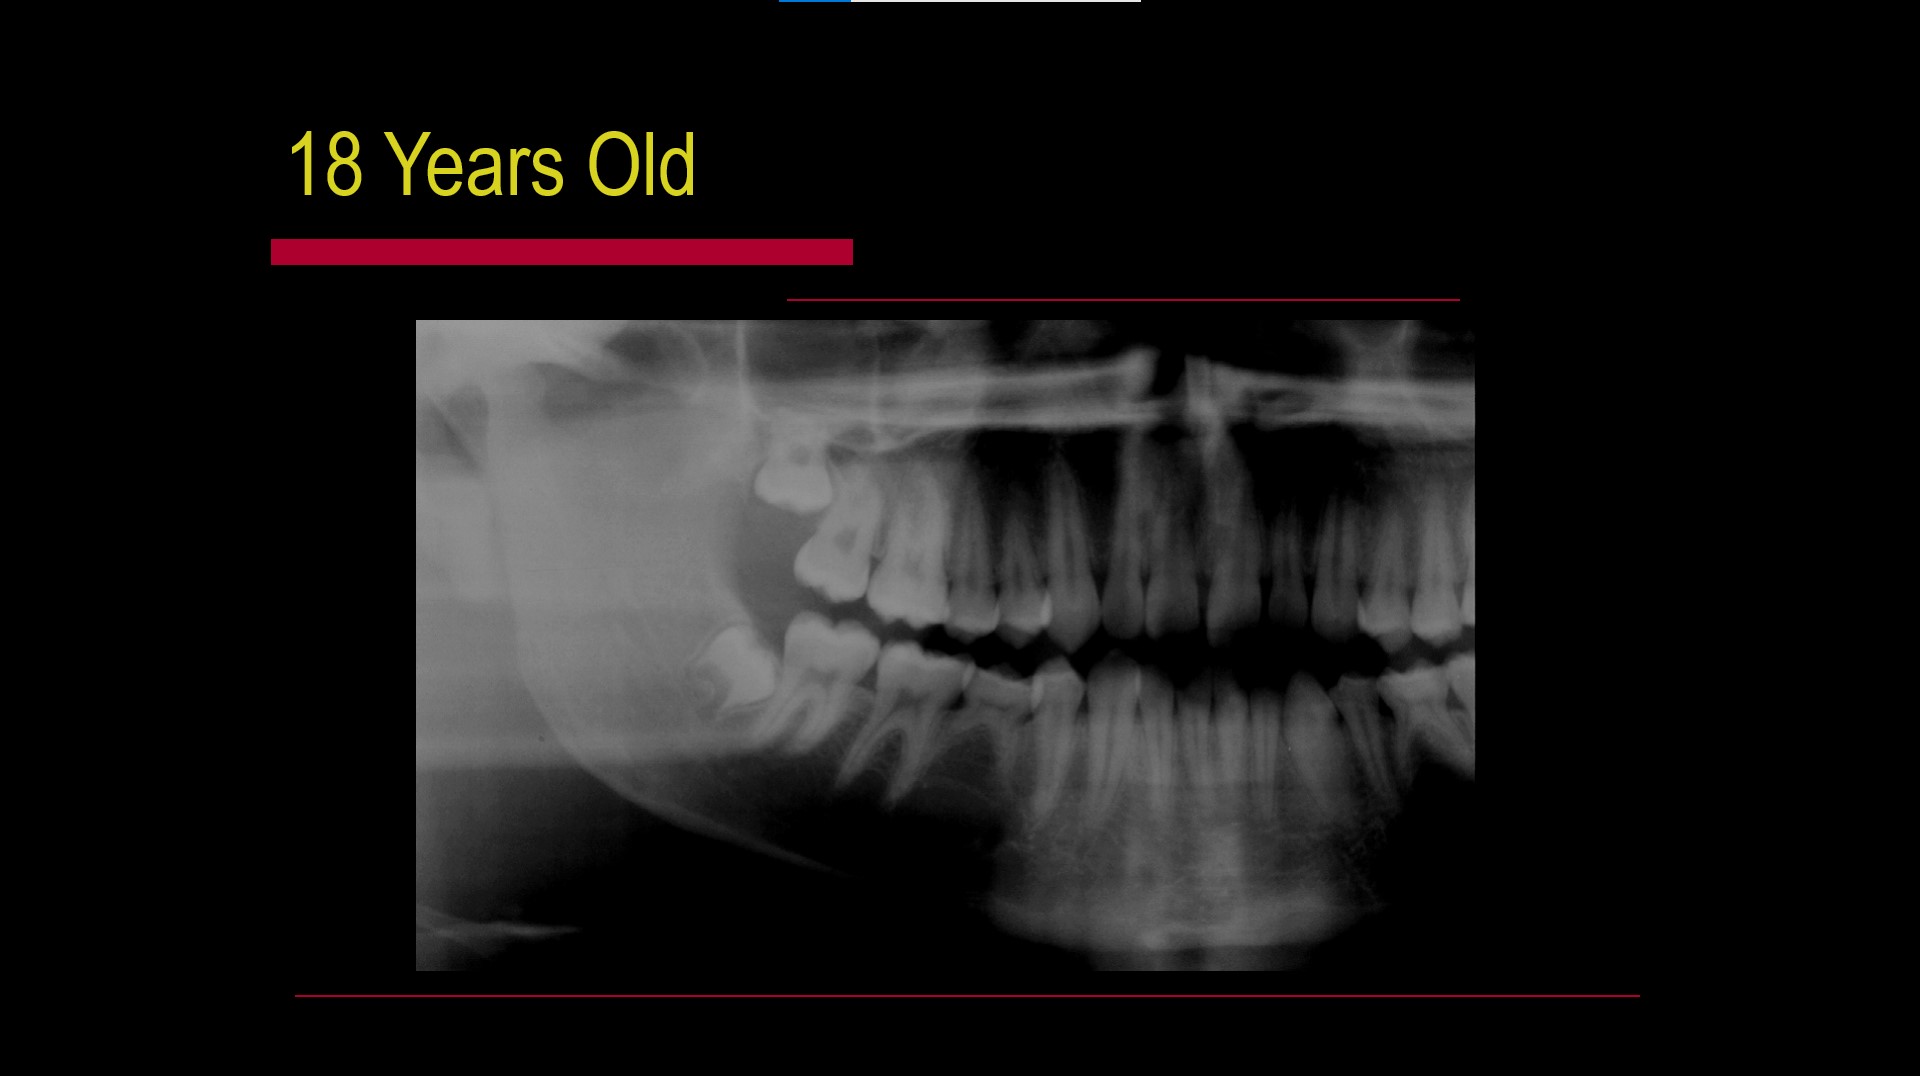

Impacted teeth